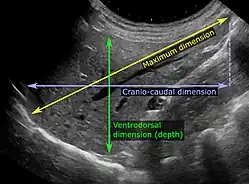

Ultrasonography of the liver with some standard measurements[6]

In patients with deranged liver function tests, ultrasound may show increased liver size (hepatomegaly), increased reflectiveness (which might, for example, indicate cholestasis), gallbladder or bile duct diseases, or a tumor in the liver.

Ultrasonography of liver tumors involves two stages: detection and characterization. Tumor detection is based on the performance of the method and should include morphometric information (three axes dimensions, volume) and topographic information (number, location specifying liver segment and lobe/lobes). The specification of these data is important for staging liver tumors and prognosis. Tumor characterization is a complex process based on a sum of criteria leading towards tumor nature definition. Often, other diagnostic procedures, especially interventional ones, are no longer necessary. Tumor characterization using the ultrasound method will be based on the following elements: consistency (solid, liquid, mixed), echogenicity, structure appearance (homogeneous or heterogeneous), delineation from adjacent liver parenchyma (capsular, imprecise), elasticity, posterior acoustic enhancement effect, the relation with neighboring organs or structures (displacement, invasion), vasculature (presence and characteristics on Doppler ultrasonography and contrast-enhanced ultrasound (CEUS).